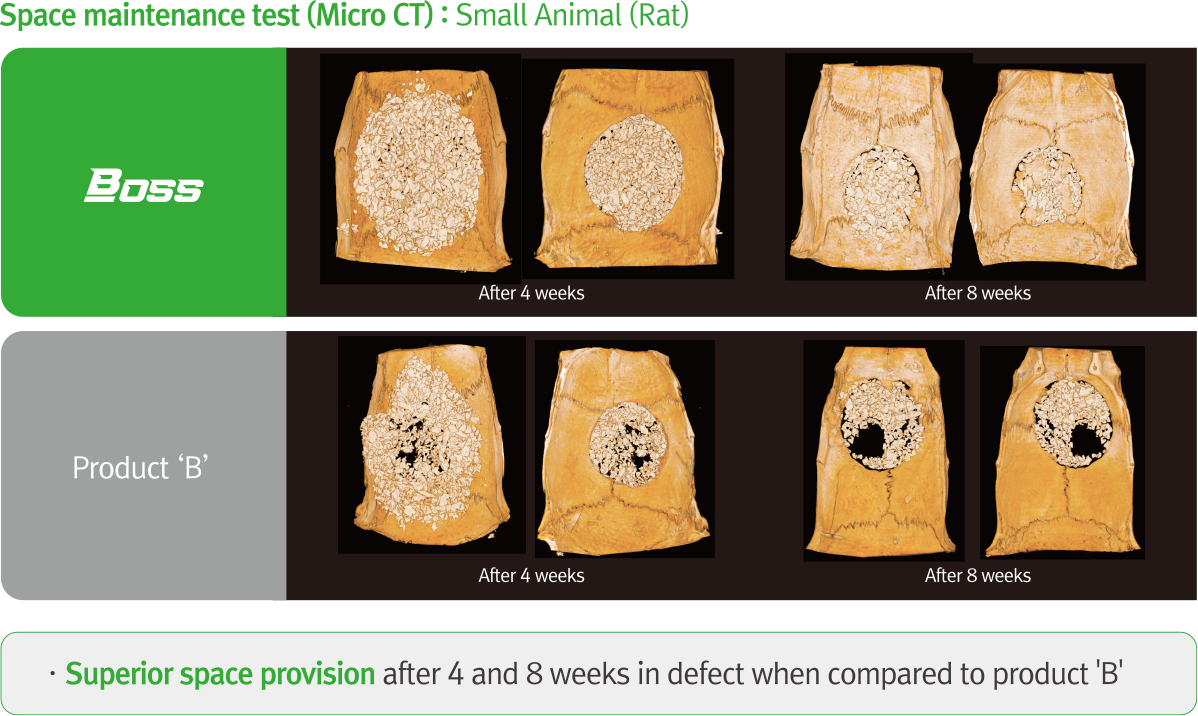

Technical Data